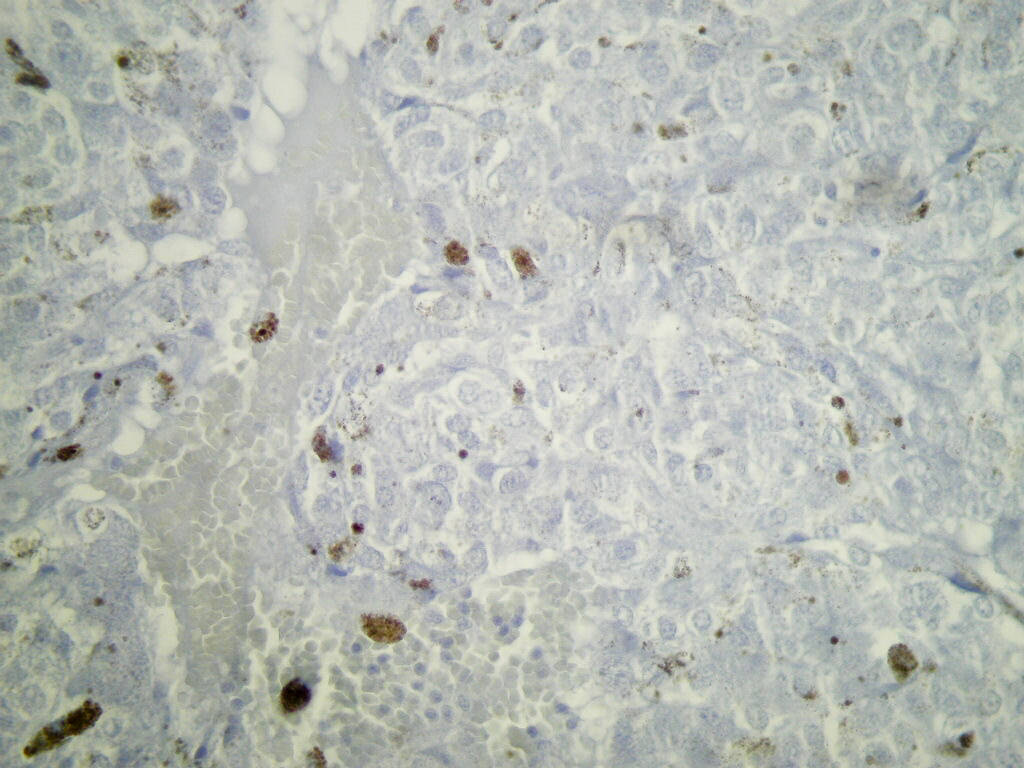

Microscopic (histologic) description

- Typical morphology: epithelioid cells with abundant, eosinophilic / amphophilic, granular cytoplasm and round / ovoid, vesicular / salt and pepper nuclei, arranged in a nested / zellballen pattern and separated by fibrovascular septae with sustentacular cells (Am J Surg Pathol 2004;28:94, World J Clin Cases 2014;2:591, Endocr Pathol 2022;33:90)

- May have focal pleomorphism, nuclear hyperchromasia, low mitotic activity or clear cytoplasm

Microscopic (histologic) images

Contributed by Theodorus H. van der Kwast, M.D., Ph.D., Michelle R. Downes, M.D., Debra L. Zynger, M.D. and David Cohen, M.B.B.Ch., M.D.

- SDHB loss (absence of granular cytoplasmic labeling) if SDHB mutation

- SDHA loss (absence of strong diffuse granular cytoplasmic labeling) if SDHA mutation

- Comment: The risk of malignancy in these lesions is estimated at 5 - 15% of cases. Malignant behavior cannot be predicted based on morphology alone and relies on the identification of metastases. Tumors associated with SDHB mutations (loss of SDHB staining) are reported to have an increased risk of metastases.

- Microscopic description: This specimen shows an unencapsulated, monomorphous population of round tumor cells in a nested / zellballen pattern with delicate vascular septa and intervening extravasated red blood cells. It predominantly involves the lamina propria of the bladder but in 1 tissue piece clearly involves muscularis propria. The tumor cells have abundant amphophilic cytoplasm and vesicular chromatin with occasional small nucleoli. There is no necrosis, diffuse growth pattern or vascular space invasion identified. The mitotic count is (maximally) 1/10 high power fields. Immunohistochemistry shows the tumor cells to be positive for GATA3 with strong and diffuse expression of synaptophysin and chromogranin, as well as retention of SDHB staining. The tumor cells are negative for AE1 / AE3, HMWK and p63. The Ki67 proliferation index is < 1%. S100 shows faint nuclear and cytoplasmic staining with occasional sustentacular cells identified.